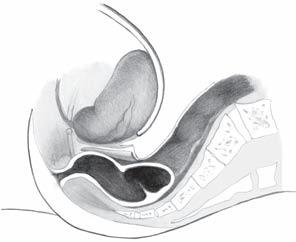

tum pod Douglasovou řasou (dolní rektum). Peritoneální řasa Douglasova prostoru je anatomicky situována do vzdálenosti 8–10 cm od perinea (obr. 2.2).

Klasické dělení rekta popisuje tři části. Ve své horní třetině má rektum peritoneální kryt vyjma partis posterior. Ve střední třetině může být kryta peritoneální řasou část přední stěny rekta, kdežto dolní třetina rekta je již vždy uložena zcela extraperitoneálně. Dělení není pouze popisné, má mimořádný význam z hlediska chirurgické techniky a prognózy tumorů lokalizovaných v těchto částech rekta. U mužů je přední plocha rekta v kontaktu s močovým měchýřem, semennými váčky, prostatou a močovou trubicí, u žen pak s dělohou a pochvou [17, 19, 20].

Obr. 2.2 Části rekta a jeho zakřivení v sagitální rovině